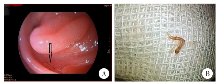

患者,男,72岁,河南南阳人,常住深圳市,有以蚯蚓为诱饵钓鱼的习惯。2023年因胃癌接受胃切除术,在例行电子胃镜复查时发现空肠部位有线虫寄生,但是无典型呼吸道及消化系统临床表现。血常规检查显示,白细胞数为6.61 × 109/L,嗜酸粒细胞百分比为0.7%,嗜酸粒细胞绝对值为0.05 × 109/L,各项指标均在正常范围内。以活检钳取出虫体。虫体呈红色,细长且呈不典型“Y”字型,长度约10 mm,可自主活动。虫体经哈瑞氏苏木素染液处理,在光学显微镜下鉴定为兽比翼线虫(Mammomonogamus)雄虫。患者被诊断为兽比翼线虫感染,采用口服阿苯达唑(400 mg/d,每日1次,疗程为1周)治疗。治疗后1周,患者粪便中未检测到兽比翼线虫虫卵。

The patient was a 72-year-old male from Nanyang, Henan Province, with a permanent residence in Shenzhen City, who had a habit of fishing using earthworms as baits. He underwent a gastrectomy for gastric cancer in 2023, and nematodes were found parasitizing the jejunum during a routine electronic gastroscopic follow-up; however, but no typical clinical manifestations of respiratory or digestive system were observed. Routine blood tests showed a white blood cell count of 6.61 × 10⁹/L, an eosinophil percentage of 0.7%, and an absolute eosinophil count of 0.05 × 10⁹/L, with all indicators within the normal range. The nematodes were removed using biopsy forceps, appearing red, slender, and atypical in shape with a “Y” configuration, measuring approximately 10 mm in length and capable of autonomous movement. Following staining with Harris’s hematoxylin, the nematodes were identified as male Mammomonogamus under an optical microscope. The patient was diagnosed with Mammomonogamus infection and orally administered with albendazole (400 mg/d, once daily for one week). No Mammomonogamus eggs were detected in the patient’s stool samples one week post-treatment.